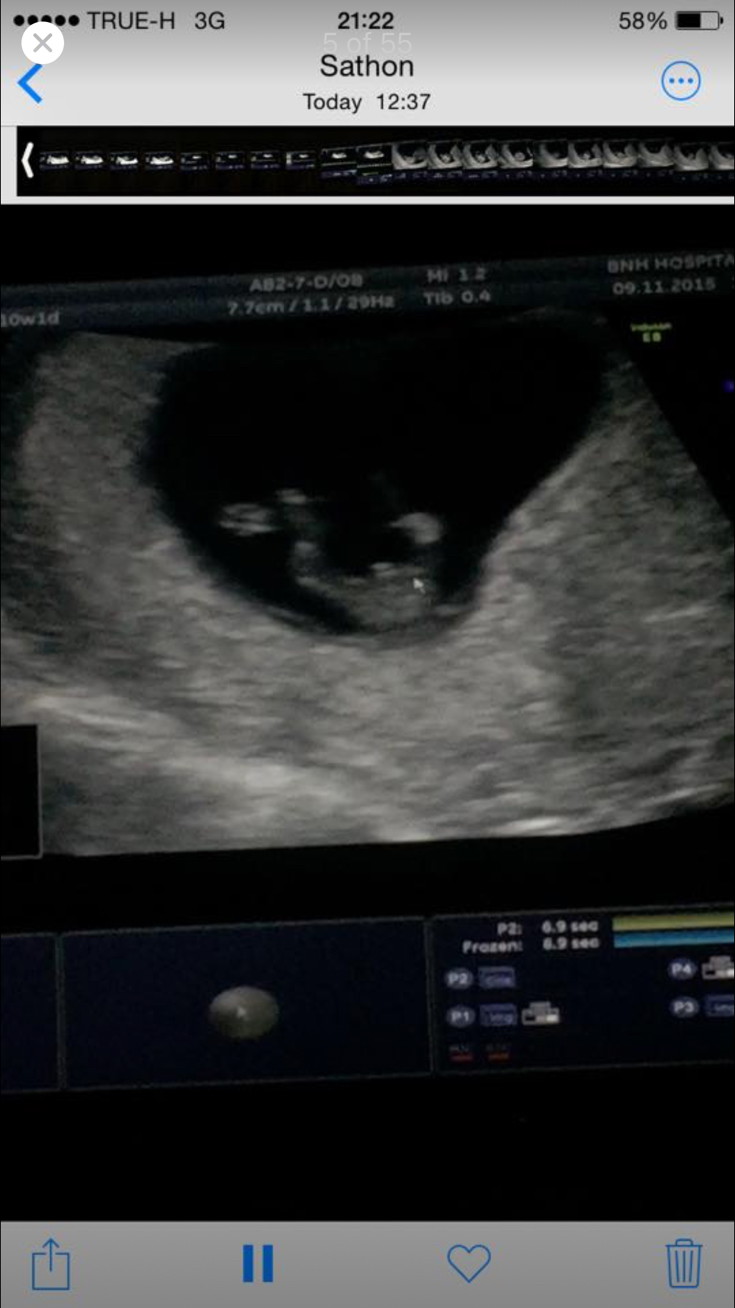

12w. มีติ่งจู๋โผล่ หมอบอกว่ามีโอกาสหดกลับได้ ยังไม่ยืนยันผช.100% แม่ๆคนไหนเจอแบบนี้แล้วกลายเป็นผญ.มั้ยคะ? #จะญ./ช.แม่ก็รัก

บางทีอาจจะยังเล็กมากๆหมอเลยยังไม่กล้าฟันธงค่ะ เพราะอาจจะเป็นสายสะดือก็ได้ รออัลตราซาวด์อีกรอบนะคะแม่ น่าจะชัวร์ค่ะ

ใช่ค่ะติ่งแบบนี้เห็นหลายคนบอกว่าน้องนอนกอดสายสะดือ มีโอกาสเป็นไปได้สูงค่ะ

ใจเย็นๆรอไปก่อนนะคะ น้องพึ่ง 12วีคเองค่ะ รอสัก16-20วีคค่ะ ถึงจะเห็นว่าเพศไหนชัดเจนนะคะ